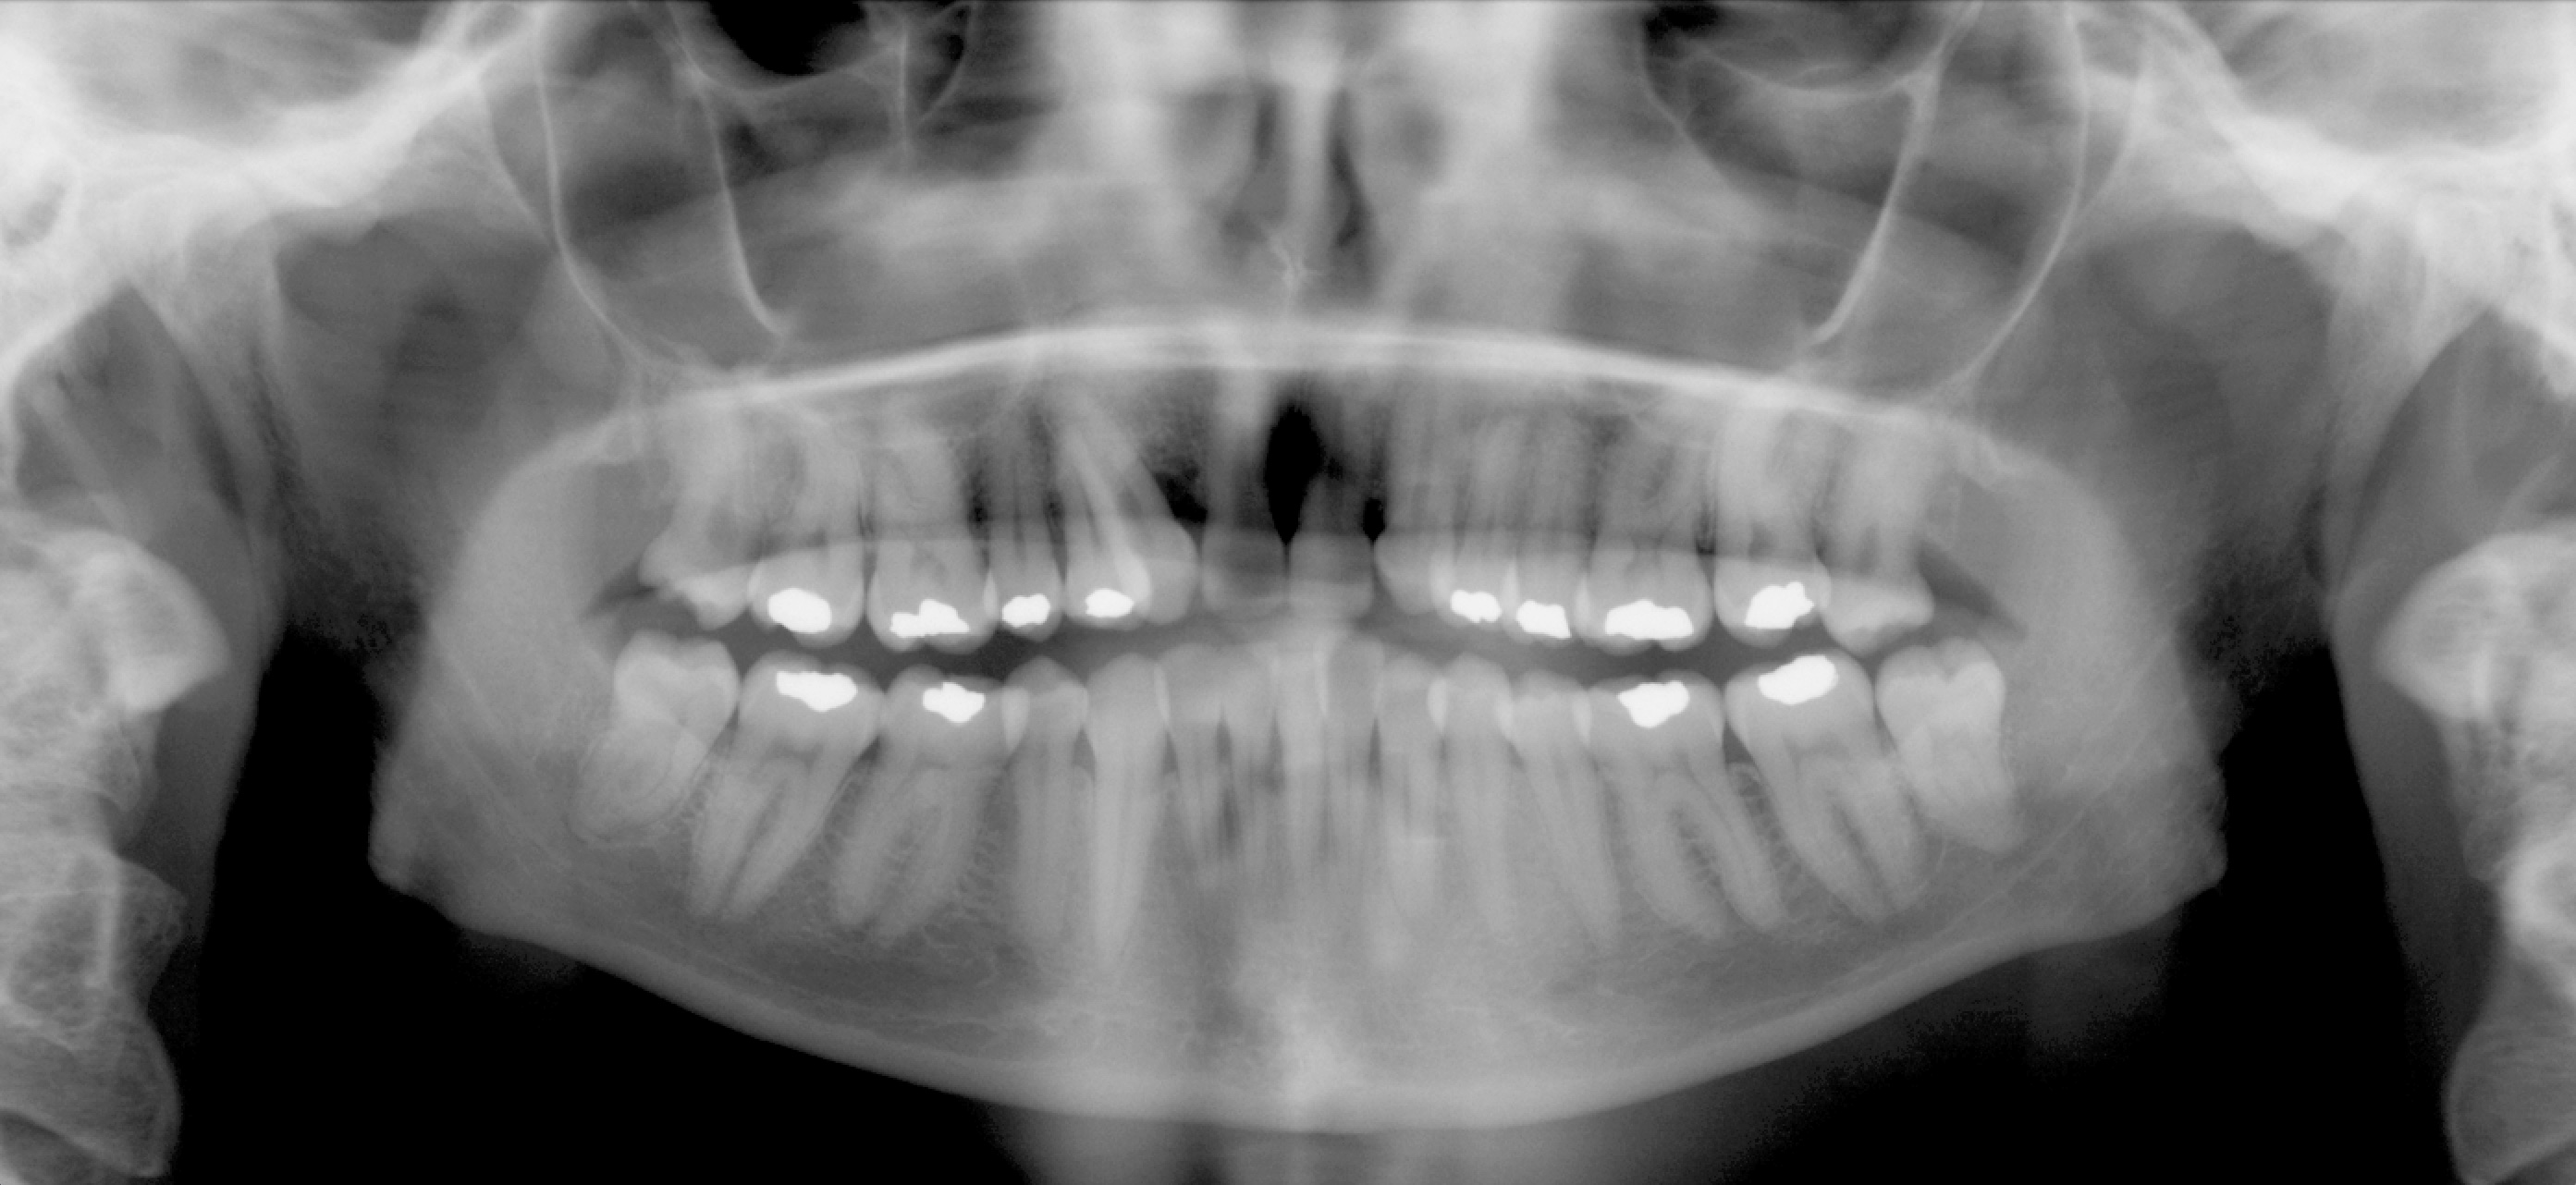

Per formulare corretta diagnosi e piano di cura, lo studio del caso ha previsto la raccolta di documentazione completa standard, ovvero fotografie del viso e intraorali (Figure 1a-e), radiografia panoramica e teleradiografia del cranio in proiezione laterale (Figure 2a-b) per la relativa analisi cefalometrica e modelli di studio.

La valutazione clinica e gli esami effettuati confermano la presenza di agenesia degli incisivi laterali superiori (1.2 e 2.2) e del secondo premolare inferiore destro (4.5).

L’analisi ortodontica e la valutazione parodontale, con particolare riferimento alla posizione della radice del canino superiore destro (1.3), distoinclinata e trasposta alla radice del primo premolare (1.4) come evidente dalla radiografia panoramica e dalle immagini intraorali, ci hanno guidati nella programmazione di un trattamento estrattivo asimmetrico a entrambe le arcate.